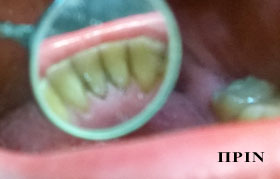

σοδοβολή